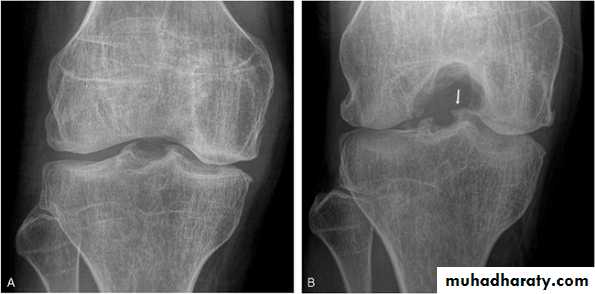

Osteochondritis dissecans of the medial femoral condyle

Osteochondritis dissecans of the medial part of the articularsurface

Osteochondritis dissecans :

affects the large articular surface , commomnly medial femural condylee ,talus and trochlea .

Ends by separation of the affected part in to the joint space resulting in intra-articular loose body .